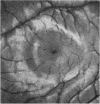

Three patients are described with foveal lesions resembling minute holes following trauma. The similarity of the lesions to foveomacular retinitis and solar retinopathy suggests that all these conditions produce a similar, localised neuroretinal lesion with sparing of the pigment epithelium. Loss of the photoreceptors at the fovea would be expected to produce a lesion resembling a small retinal hole.